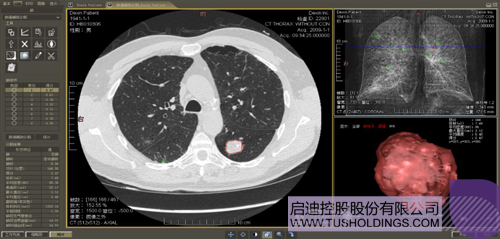

數字肺產品肺癌計算機輔助診斷

醫療影像智能分析是指運用人工智能技術、計算機視覺技術以及計算幾何技術對醫療影像進行自動分析,幫助醫生定位病癥、分析、跟蹤病情,并通過量化數據輔助醫生做出診斷,目前其旗艦產品“數字肺”已經覆蓋多種肺部疾病的早期檢測、診斷、跟蹤、術前規劃等完整的醫療流程。在臨床實踐中,超過80%的醫療數據來自醫療影像,這些影像數據通常需要專業醫生進行解讀,工作的重復性高、效率偏低。如果能夠運用智能影像分析技術,同時結合臨床表現以及既往病例進行全面分析,那么就可以大幅度提升影像診斷效率和準確性,讓專業醫生的寶貴時間集中在復雜病情的診斷和治療等環節。

肺動脈栓塞輔助診斷